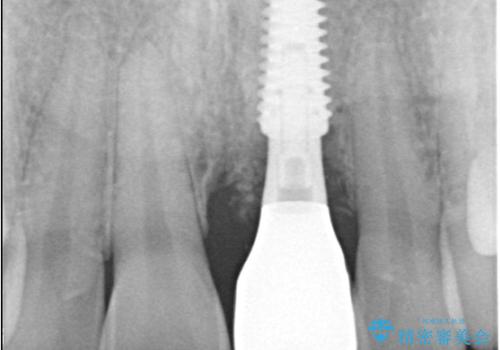

- 歯頚部外部吸収により抜歯適応の歯を抜歯して即時にインプラントを埋入したケースです。

歯肉が下がっていることを気にされていたため、できるだけ考慮して術式を決めて治療を行いました。

インプラントの手術は二回になることが多いですが、1Dayインプラントの場合は手術は一回で済みます。